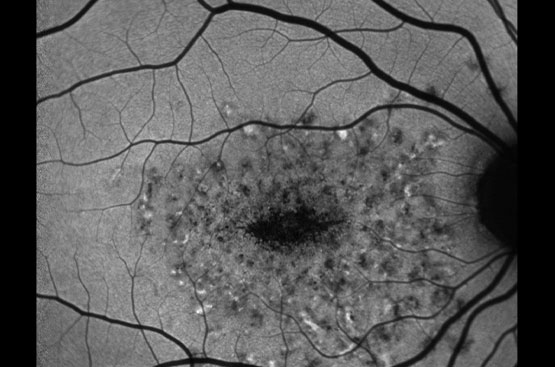

OCT-Angiografia (Angio-OCT)

Rendering HD della circolazione maculare per screening e prevenzione della maculopatia e studio delle patologie vascolari e delle occlusioni arteriose e venose